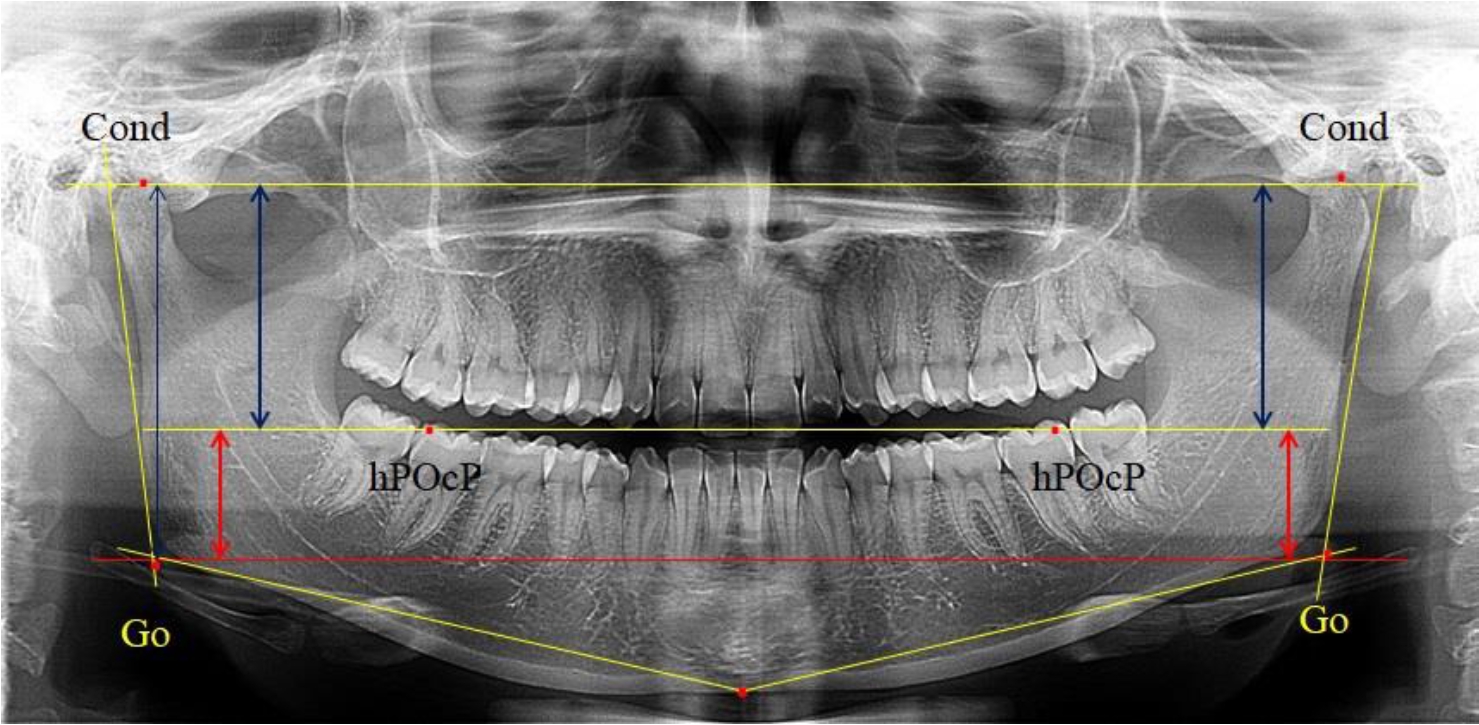

3-я подгруппа была с наименьшим количеством анализируемого материала, и здесь было проанализировано 17 комплектов рентгенограмм [(22,97 ± 4,89) %], на которых средняя величина отношения верхней части ветви к нижней составляла 2,45 ± 0,04, что было достоверно больше показателя, полученного по группе в среднем, а также в 1-й и 2-й подгруппе. Визуально параметры ветви отличались от других подгрупп. Высота ветви составляла (57,83 ± 0,89) мм, что было несколько меньше, чем в других подгруппах. Максимальная высота была 64 мм, а минимальная – 53 мм. Высота верхней части составляла (41,03 ± 0,59) мм, что было близким по значениям, полученным в других подгруппах и свидетельствовало о меньшей вариабельности указанного параметра. В то же время высота нижнего отдела ветви была (16,83 ± 0,36) мм и показатель отличался в меньшую сторону, по сравнению с аналогичным размеров в других подгруппах (рис. 4).

Таким образом, при физиологических вариантах прикуса определены основные вертикальные параметры ветви нижней челюсти и ее составных частей. В среднем высота верхней окклюзионно-суставной части ветви в два раза превышала размеры нижней окклюзионно-гониональной части, что может быть использовано как в клинике ортодонтии, так и челюстно-лицевой хирургии при планировании операций по моделированию ветви нижней челюсти.

Рис. 4. ОПТГ пациента 3-й группы с увеличенным коэффициентом соотношения частей ветви нижней челюсти